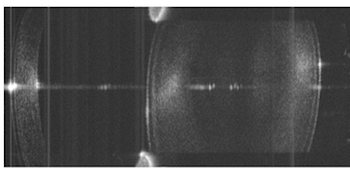

Quasi-simultaneous imaging of the whole eye was achieved using the retinal imaging configuration, but moving the ETL and offset lens further back to provide greater beam divergence. From that position, the resulting beam at the pupil plane could be either collimated (via low ETL current) or focused (high ETL current), with images of the anterior segment and retina acquired alternately.

This approach tackles the major barrier in development of whole-eye imaging systems, the impossibility under normal circumstances of focusing light on both areas of interest due to the natural refractive power of the eye itself.